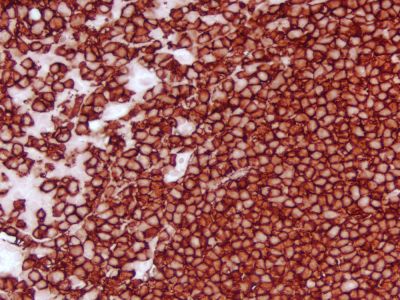

?The ImmPRESS polymerized reporter enzyme staining system uses novel conjugation and micropolymer chemistries to create a highly sensitive, ready-to-use, one-step, non-biotin detection system for immunohistochemistry and immunocytochemistry staining. This unique micropolymer of highly active horseradish?peroxidase (HRP)?is attached to our affinity purified secondary antibodies, producing reagents with outstanding sensitivity and low background.

The peroxidase micropolymers of the ImmPRESS HRP polymer reagent limit steric interference and provide enhanced accessibility to the target, avoiding the disadvantages of other polymer systems that use large dextrans or other macromolecules as backbones. The result is crisp, strong staining of antibody targets, especially nuclear and membrane antigens (such as Ki67, estrogen receptor, bcl-2, CD3, CD8 and CD10) and greater sensitivity than other polymer systems.